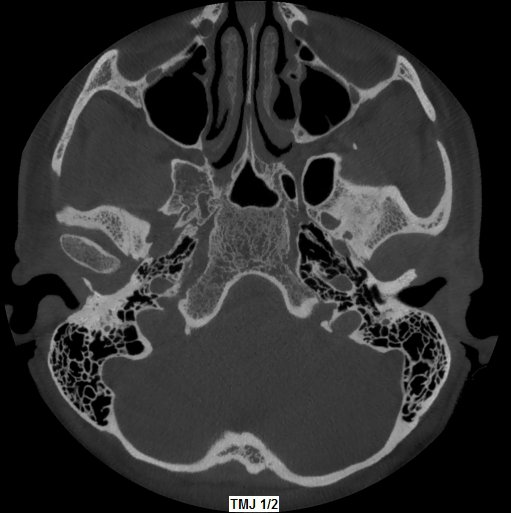

Rottura del pavimento del Seno Mascellare sinistro con Sinusite